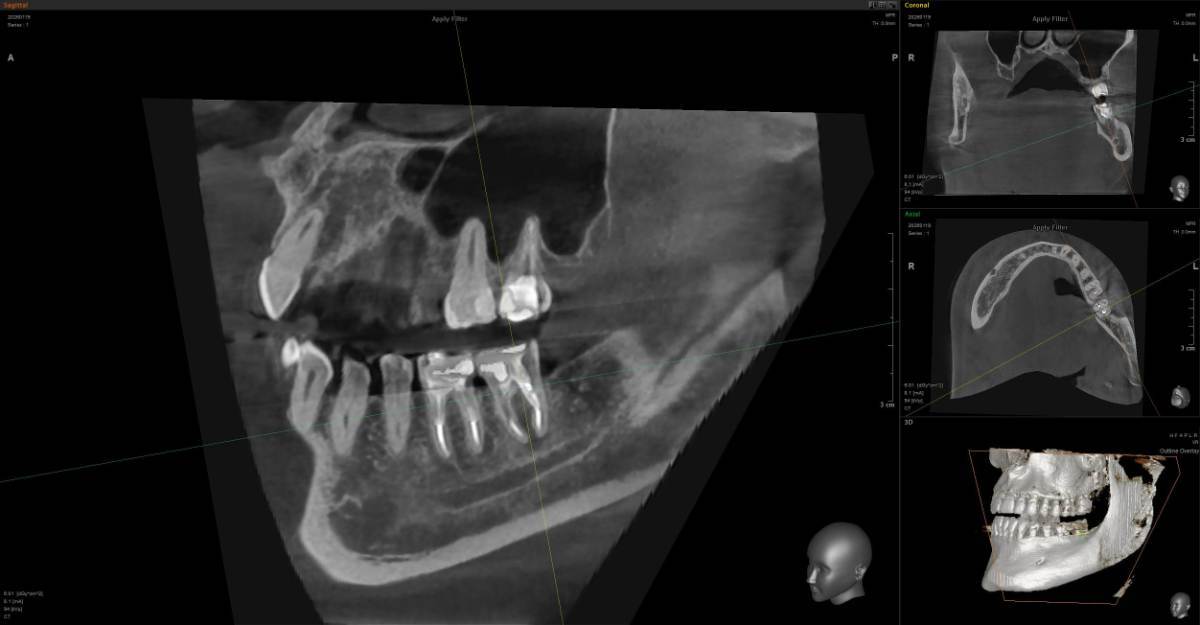

A-V-S Опубликовано 3 марта Поделиться Опубликовано 3 марта Здравствуйте. У меня такая ситуация: В начале января 2026 начал болеть зуб 7ка снизу слева - боль развивалась постепенно - в итоге стало больно жевать. Сделал КТ. Лечащий стоматолог сказал, что это проснулось спящее воспаление, перелечивать каналы зуба сложно - надо сверлить буром и доставать стекловолоконный штифт - надо удалять. В следующие дни открылся свищ и боль ушла. Свищ продолжает быть с периодическим набуханием и сдуванием после выброса гноя белого цвета. Этот зуб лечили с установкой стекловолоконного штифта чуть больше 5 лет назад. Посмотрите, пожалуйста, приложенные снимки и посоветуйте как быть - можно ли перелечить и сохранить зуб ? Ссылка на комментарий

АнтонТЛТ Опубликовано 3 марта Поделиться Опубликовано 3 марта Добрый вечер, лучше выложить несколько срезов этого зуба, либо архив с кт. По представленным снимкам, есть подозрение о наличии трещины между корнями зуба. 1 1 Ссылка на комментарий

red_butler Опубликовано 4 марта Поделиться Опубликовано 4 марта Здравствуйте, Вы выложили не срезы. а реконструкцию. Залейте кт в облако и скиньте сюда ссылка на скачивание Ссылка на комментарий

Гарриевич Опубликовано 6 марта Поделиться Опубликовано 6 марта Не знаю обрадует Вас это или огорчит, но зуб можно сохранить соседний тоже с воспалением кстати 1 1 Ссылка на комментарий

red_butler Опубликовано 9 марта Поделиться Опубликовано 9 марта В 03.03.2026 в 22:49, A-V-S сказал: можно ли перелечить и сохранить зуб ? можно Ссылка на комментарий

A-V-S Опубликовано 9 марта Автор Поделиться Опубликовано 9 марта @Гарриевич , @red_butler . спасибо. В 06.03.2026 в 21:28, Гарриевич сказал: соседний тоже с воспалением кстати @Гарриевич , на соседнем свища нет. Тоже надо перелечивать вместе с 7 ? Ссылка на комментарий

red_butler Опубликовано 10 марта Поделиться Опубликовано 10 марта 11 часов назад, A-V-S сказал: на соседнем свища нет. Тоже надо перелечивать вместе с 7 ? да Ссылка на комментарий

Doc Опубликовано 10 марта Поделиться Опубликовано 10 марта 16 часов назад, A-V-S сказал: на соседнем свища нет. Тоже надо перелечивать вместе с 7 ? Отсутствие свища не снимает проблемы наличия кисты на этом зубе. Рано или поздно будет вам свищ, либо зуб так заболит, что придется удалять безо всякого свища. 1 Ссылка на комментарий